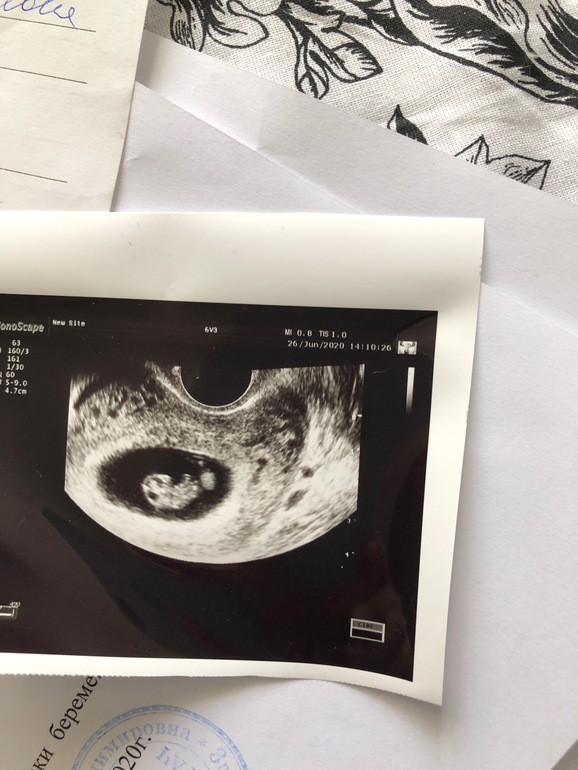

Дядя Рамзи не учёл такого поворота событий 🤷🏻‍♀️🤣 Ну а серьезно, по картинке-узи всёравно где-то есть лево или право😅 просто кто там право, а кто лево, если ПЯ же не плоское, это ж пузырь! Мне на втором узи ели второго эмбриона нашли, он прятался... так что, какой там лево/право... 😂🤭 Да по узи у автора явно ЖМ визуализируется, эмбриона на картинке не видно 🙈

Тут малыш справа 😀тут где то 9 неделя

По рамзи смотрят именно 6-8 недель чтоли ? 🙈

если вагинальное узи то мальчик слева,если узи по животу то справа